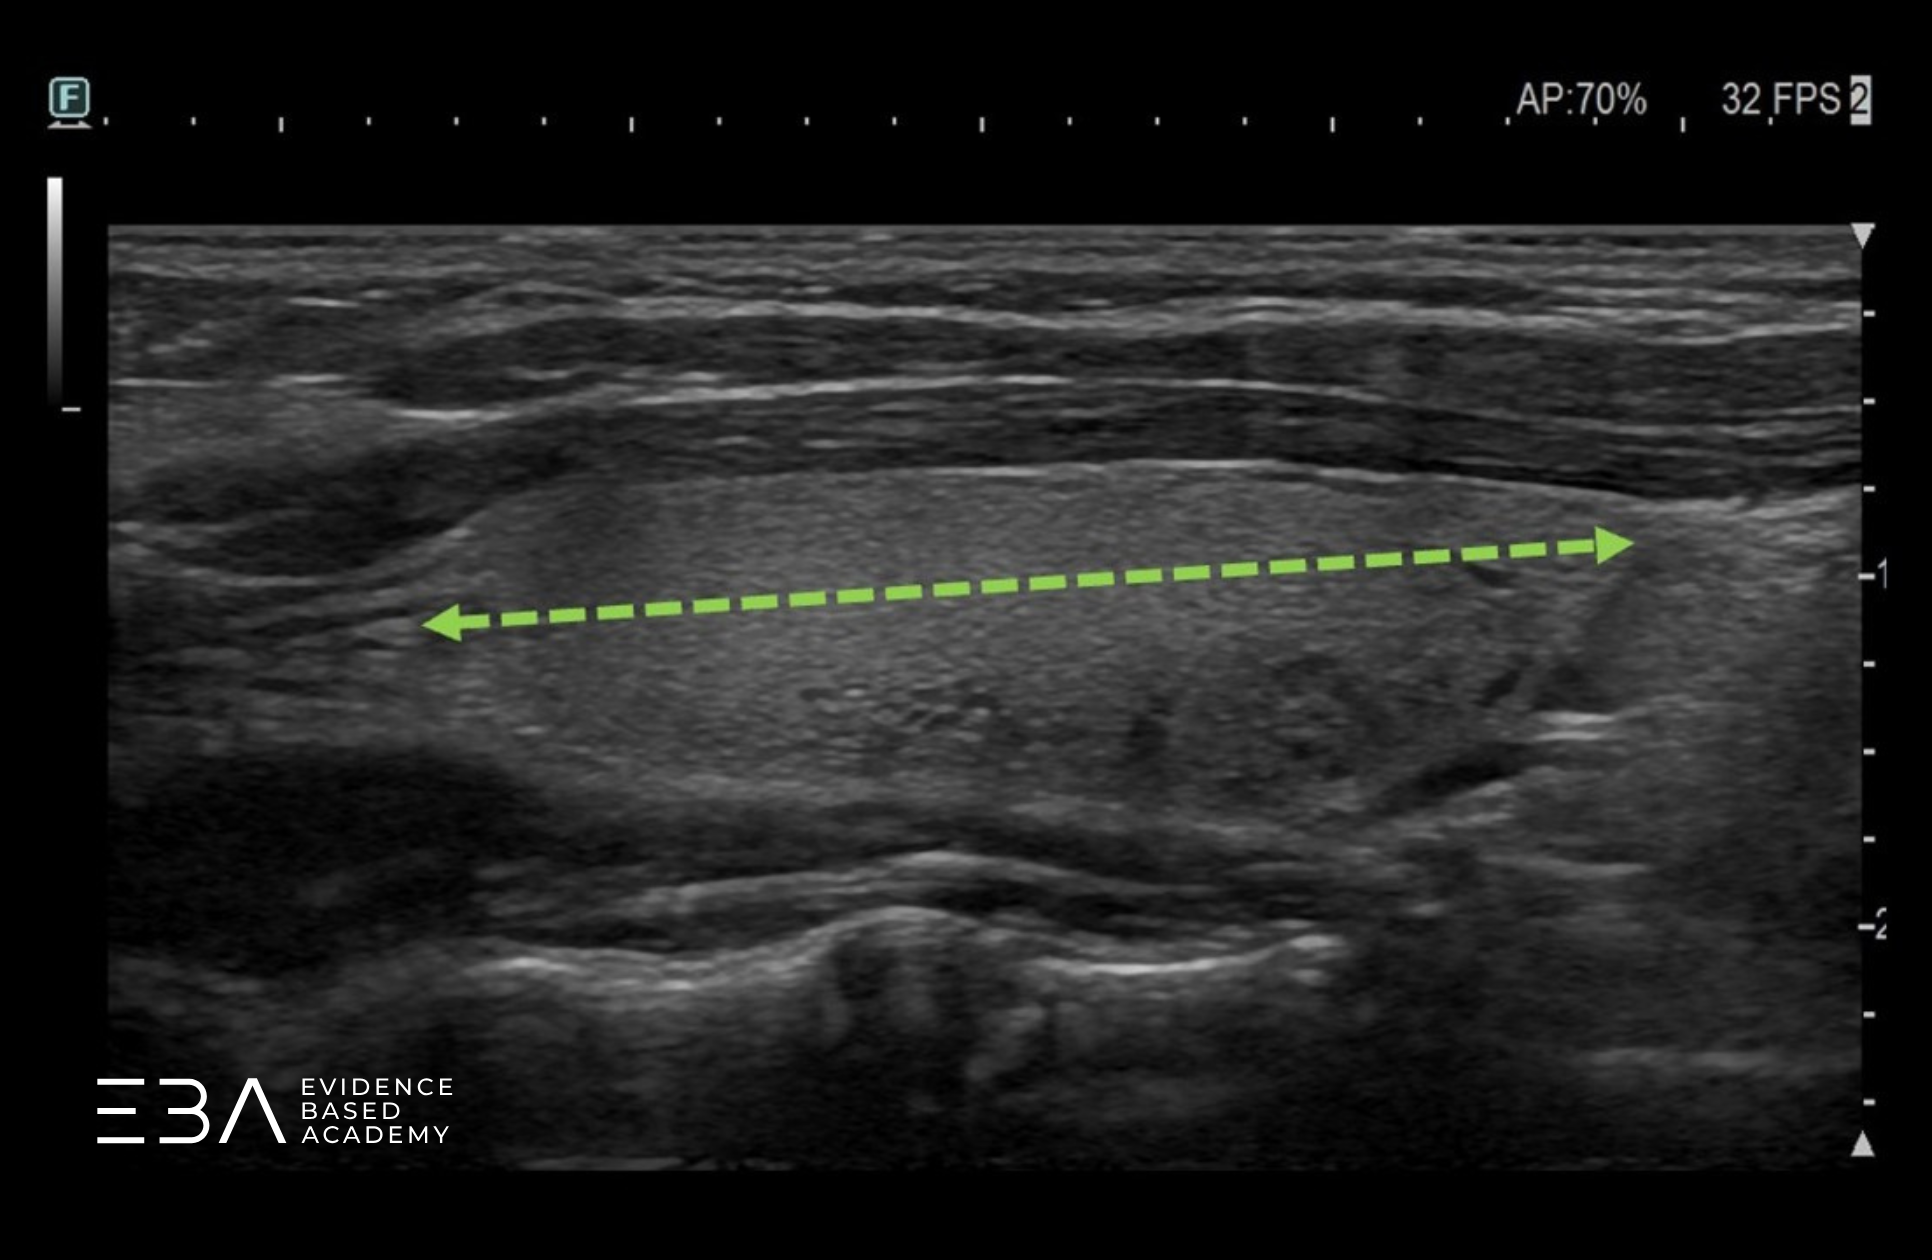

W projekcji podłużnej możemy podzielić płat na trzy części. Po lewej stronie obrazu (po stronie znacznika) widoczna jest część górna (inaczej biegun górny), na środku – część środkowa, a po prawej stronie obrazu – część dolna (inaczej biegun dolny).

Projekcja podłużna z podpisami części płata.

W projekcji podłużnej możemy również wyodrębnić część przednią, bliższą czoła głowicy (część brzuszną) oraz część tylną (grzbietową). Podział tarczycy na poszczególne części jest orientacyjny i służy głównie do opisu lokalizacji zmian ogniskowych widocznych wewnątrz tarczycy lub w jej okolicy.

Projekcja podłużna z podpisami zarysu przedniego i tylnego.